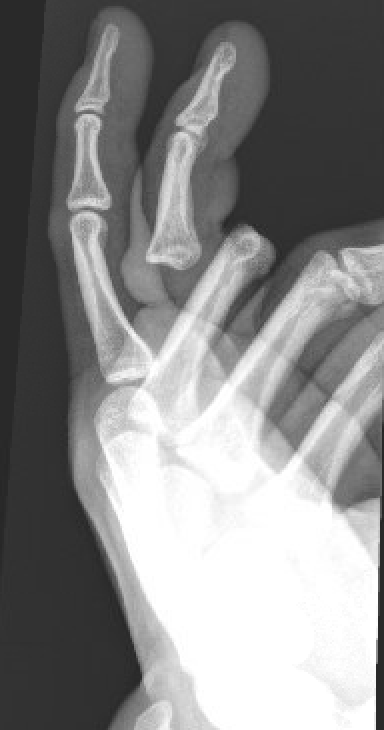

The images below demonstrate an open fourth digit proximal interphalangeal joint dislocation.

open finger dislocation open finger dislocation